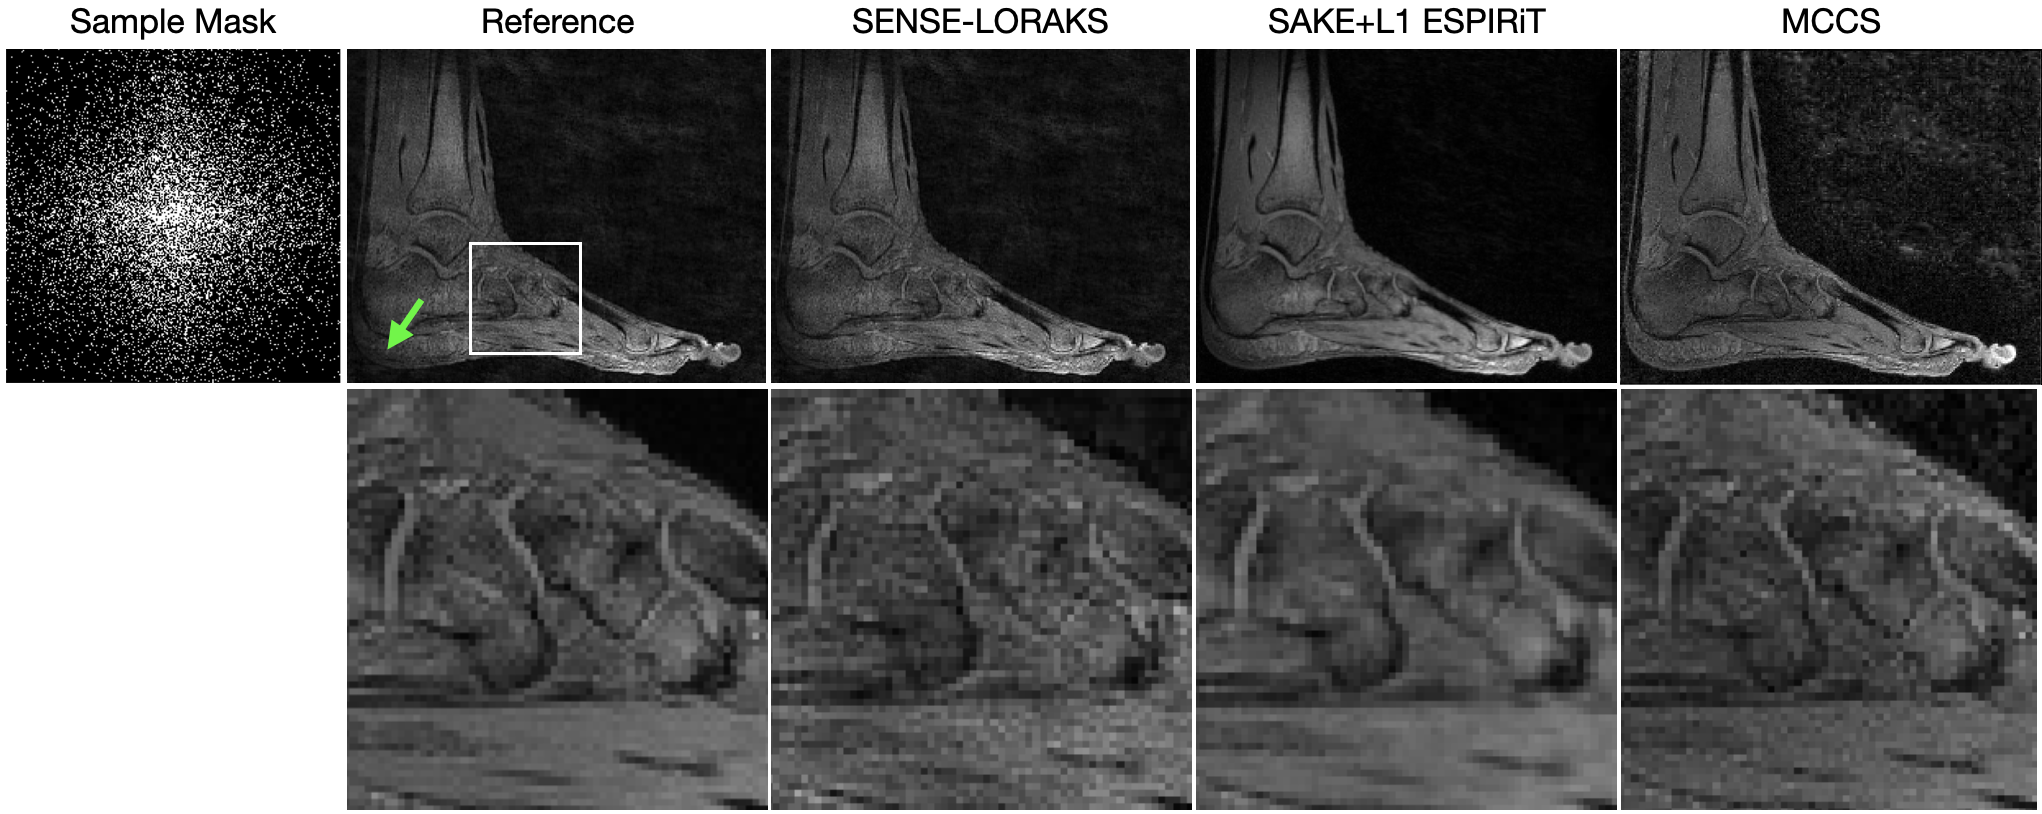

Figure 7 shows reconstructions of the ankle using data collected from a 333 Tesla scanner with an 3-element ankle coil. The regularization parameter used for SAKE+L1 ESPIRiT was 2.51032.5superscript1032.5\cdot 10^{-3}. The regularization parameters used for MCCS were λx,λs,λh)=(100,100,109)\lambda_{x},\lambda_{s},\lambda_{h})=(10^{-0},10^{0},10^{9}).

At a gross level, one notes that the amount of noise present in the MCCS reconstruction is less than that of the SENSE-LORAKS reconstruction. The intensity throughout the anatomy is more uniform with MCCS than with the other reconstruction methods; this is highlighted by the more distinct outline of the heel, as indicated by the green arrow in the reference image. Note that the tissue of the heel in the MCCS reconstruction is more similar to tissue of the same type in the rest of the ankle, even when compared to the reference image (where the heel is darker than it should be). When observing the zoomed in region in the second row, note the reduced noise of MCCS over SENSE-LORAKS and the increased detail of MCCS of SAKE+L1 ESPIRiT.

Figure 7: The left column presents a reconstruction with 100% of the samples for reference. The other columns present reconstructions using SENSE-LORAKS, SAKE+L1 ESPIRiT, and MCCS with 15% of the data require for full sampling (that which satisfies the Nyquist-Shannon theorem). The green arrow points to the heel of the foot, which is most similar to surrounding tissue in the MCCS reconstruction (even more than the reference). The second row zooms into the region shown in the white box of the reference image.